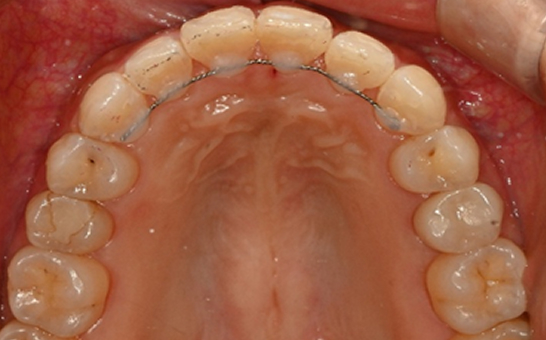

인비절라인 퍼스트(Invisalign First)는 어린이와

성장기 청소년을 위한 투명 교정 장치로, 치아와 턱뼈가

성장하는 과정에 맞춰 설계된 교정 시스템입니다.

해당하는 증상이 있다면 전문의와 상담 후 조기 교정 시

성장기 어린이에게 교합이 틀어지는것을 미리 예방 할 수 있습니다.

※ 바른선택치과의원은 의료법을 준수하며 위 케이스는 실제 내원 환자분의 동의하에 공개된 사진과 동일한 환자분께 같은 조건에서 촬영한 사진을 활용했습니다.

개인에 따라 진료 및 치료 방법이 다르게 적용할 수 있으며, 효과와 부작용이 개인마다 다르게 나타날 수 있는 점을 안내해 드리며, 진료 전 전문의료진과 충분한 상담을 권해드립니다.